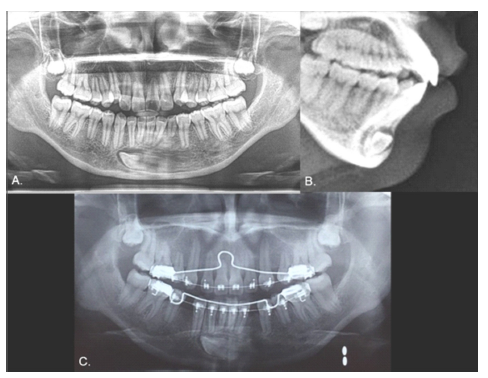

Case 2

Female, 15 years old. As with Case 1, the inferior left canine was the only primary tooth remaining in the mouth (Fig. 3). The radiograph showed that the 3.3 exhibited a type 2 transmigration (Figs. 4, A and B). The tooth was located closer to the mandible edge than in Case 1, precluding the use of orthodontic traction, and it was decided to monitor the tooth. Dental protrusion was the initial reason for the appointment, and the patient requested orthodontic treatment of this condition. Because the 3.3 was far from the roots of the neighboring teeth, the orthodontist decided there would be no risk in moving teeth in this zone. To correct the protrusion, the first premolars were extracted (except for quadrant 3 since the 3.3 was transmigrated). The 3.3 would not be restored in this treatment since the 3.4 would take its place. The 1-year follow-up panoramic x-ray showed no significant changes (Fig. 4C).